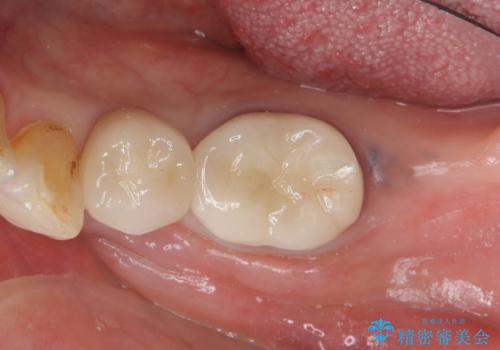

70代女性 段差のある被せ物のやり替え

左上56間が狭かったため、写真にはないですが、セパレーションを2回ほど行い、歯根間距離を広げてから処置を行っています。

歯と歯の間(特に歯根と歯根の間)が異常に狭いと歯型が正確にとれない上に歯間ブラシも入らないような歯の形態になり、セルフケアに支障がでてきます。

そのまま無理やり歯型を取って製作するよりも、ご自身で清掃ができる形態にできるため、長期的な予後が期待できます。